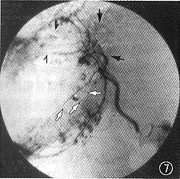

图7 例4。取代性肝右动脉(发自肠系膜上动脉)DSA动脉期像隐约可见巨大CHL下部和上部簇集血管湖周围早显的、伴顺行血流的引流静脉(

和

),肝静脉支早显(↑)

图8 例4。门静脉后期像清晰显示瘤体下部和上部的引流静脉(

)注入肝静脉(↑),并见经肝包膜下静脉的回流(

),门静脉主干还隐约可见(

)